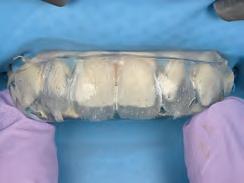

After developing the simulated mock-up, a 3D-printed resin model was created using CAD software (Fig 4a), and a clear PVS matrix (Exaclear, GC America) was fabricated to replicate the printed diagnostic wax-up using a nonperforated tray (Fig

4b). This matrix was used to create an intraoral motivational mock-up with bis-acryl composite (Luxatemp Ultra, DMG). This additive mock-up provides the interdisciplinary team with an intraoral translation for evaluation (Fig 5). Upon evaluation of the digital smile frame and the clinical translation, it was determined that multiple esthetic and restorative requirements were necessary for an optimal biologic framework, and the interdisciplinary team determined the best sequence for these procedures. The patient was presented with the interdisciplinary treatment possibilities that included restoring the maxillary anterior teeth and premolars with a minimally

invasive preparationless procedure or with less conservative veneer preparations. The restorative materials discussed included injectable resin composites and ceramic (ie, feldspathic, pressable, machinable). For an optimal biologic framework and health, it was determined that connective tissue grafting would be necessary for treatment of the recessiontype defects on the maxillary left central and lateral incisors, canine, and premolars. The patient opted for the conservative preparationless composite veneers using the injectable resin technique followed by a connective tissue surgical procedure using the tunneling technique.